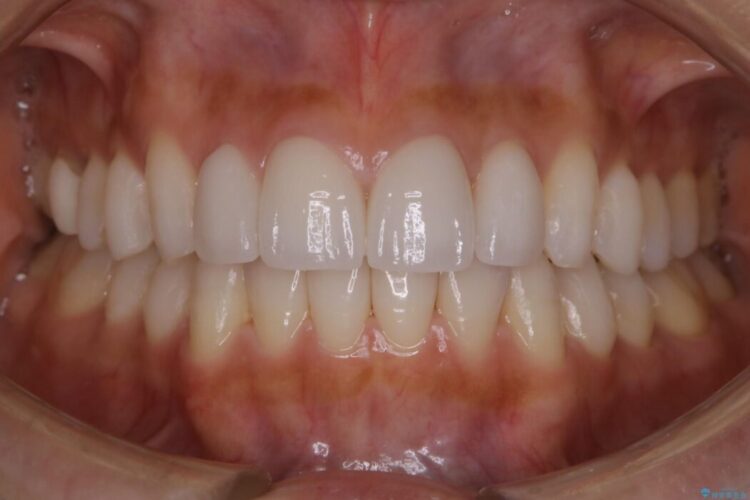

既定のインビザラインの装着時間を守っていただけたこともあり整ったアーチとなりました。

特に気にされていた噛み合わせは改善されご満足いただけました。